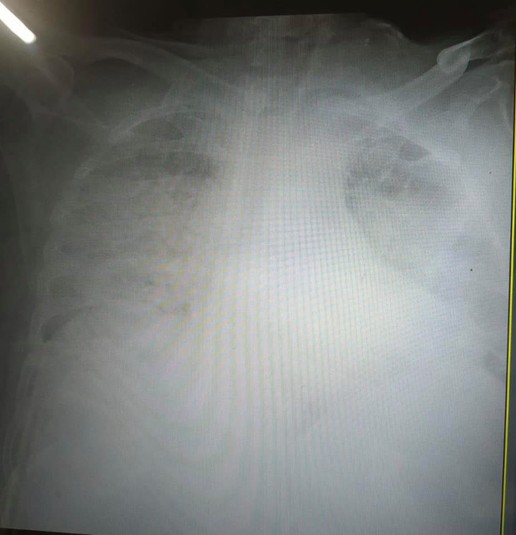

«Це одні з найстрашніших легень, які я бачила в житті», – сказала очільниця реанімації

Львівські лікарі показали фото, як виглядають легені у пацієнтів, які мають тяжкий перебіг коронавірусу.

«Це одні з найстрашніших легень, які я бачила в житті», – сказала мені щойно очільниця реанімації клінічної лікарні швидкої медичної допомоги Львова», – розповіла журналістка.

Заславець додала, що до вищевказаного медзакладу у Львові привезли 18 хворих на коронавірус пацієнтів із Винників. Семеро із них знаходяться у критичному стані у реанімації.